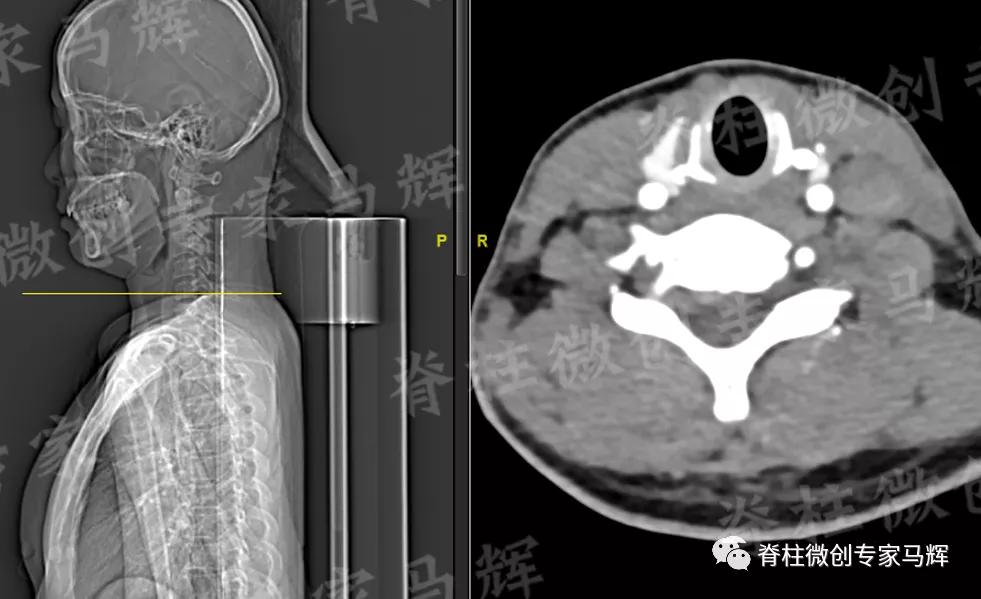

马主任仔细给患者做了检查,发现疼痛范围累及颈背部,及右上臂、前臂至手掌桡侧三指,无胸背部束带感,无行走不稳。根据影像学结果,诊断缪女士患6/7椎间盘突出症,属于神经根型颈椎病。

(术前)